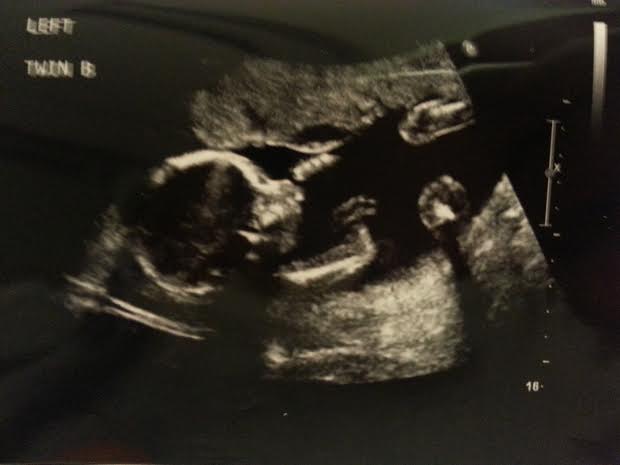

These two little ladies have already seemed to develop personalities of their own, even though they weigh only slightly more than a pound. They may be identical, but their attitude towards living in my easy bake oven seems totally different.

Meet Twin A, she’s the one you’ll find nestled in my side, often turning peacefully, but usually hiding. Her sister, Little Miss Twin B, is a trouble. maker. Seriously. Feisty as can be, whenever she is expected to perform in her ultrasound checks, she swims away and does everything to avoid the camera. She’s also much more active, constantly kicking and punching me.

While both girls seem to have already started developing their unique personalities and life perspectives, they are also already fighting. One ultrasound showed Twin A kicking her sister, while Twin B punched back.